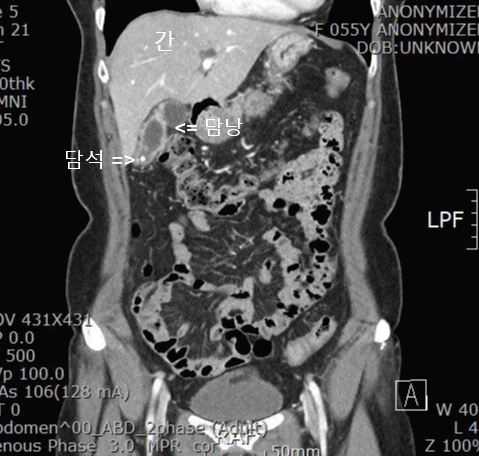

수술전에 해부학적 구조를 확인하기 위해 복부 CT를 시행했습니다.

간 아래쪽으로 담낭(Gall bladder)이 보입니다. 담낭벽이 만성 염증으로 두꺼워지면서 희게 보입니다. 만성 담낭염 소견입니다. 또 담낭안에 하얀 점으로 보이는 담석도 확인됩니다. CT 판독은 만성 담석성 담낭염(Chronic calculous cholecystitis) 소견입니다.